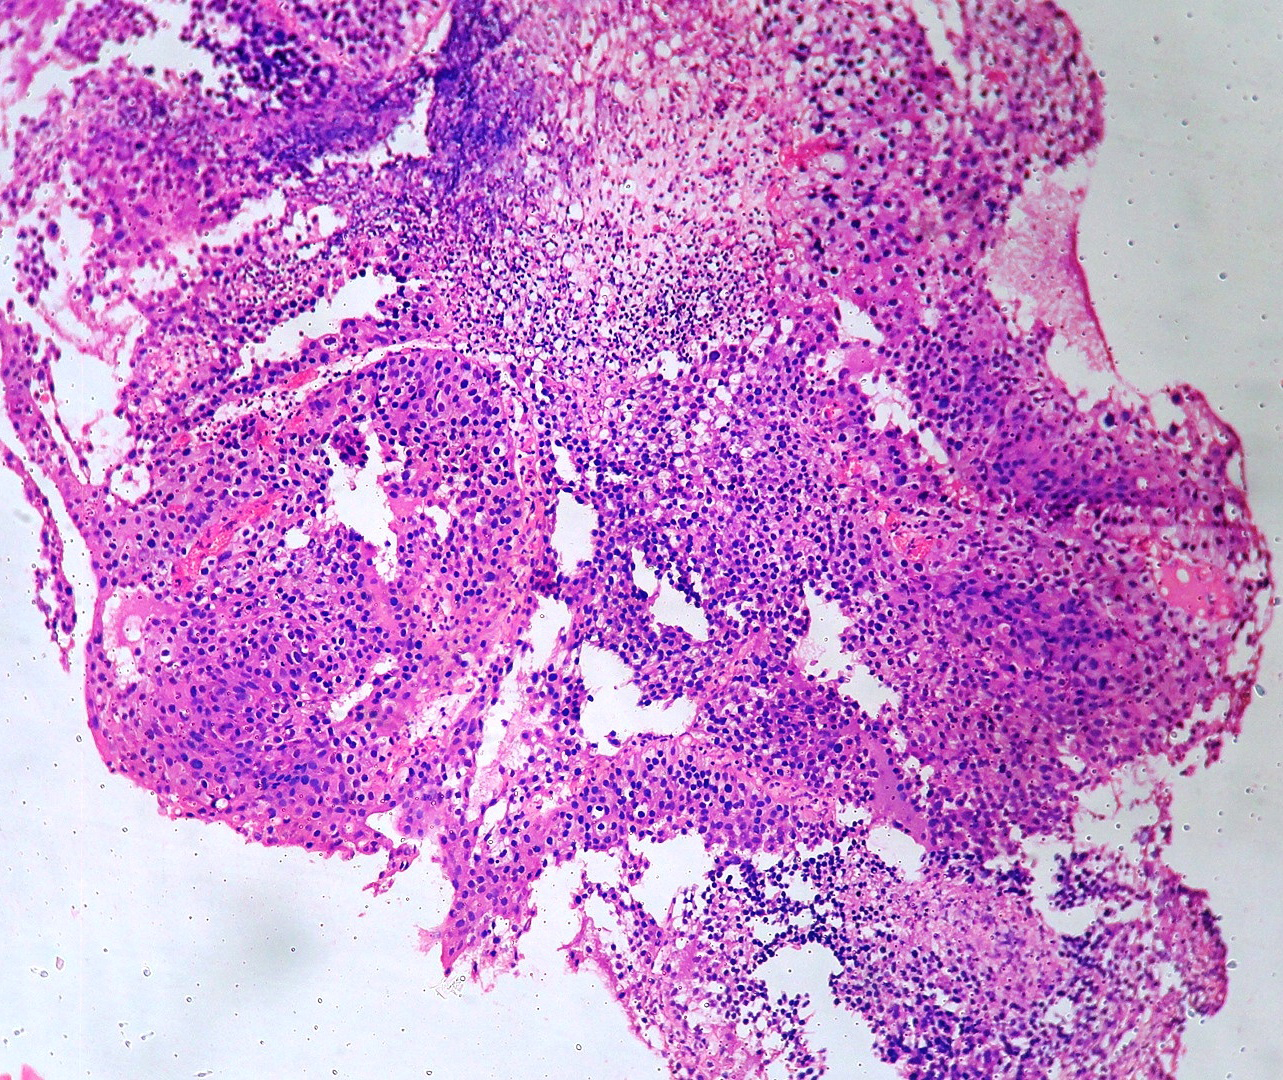

In our study, we made an attempt to evaluate the pattern of tumor growth, its degree of differentiation, progression and associated mucosal changes. In 15 cases of urothelial papilloma, it is characterized by discrete papillary growth with a central fibrovasular core lined by urothelium of normal thickness and cytology (Figure 1). In five cases of Papillary urothelial neoplasm of low grade malignant potential (PUNLMP), histopathologically the tumor is characterized by delicate, orderly, tenuous papillary structures with orderly arrangement of cells within the papillae with minimal architectural abnormalities and nuclear atypia usually limited to basal layer irrespective of cell thickness (Figure 2). The major distinction from papilloma is that in PUNLMP the urothelium is much thicker and nuclei are significantly enlarged. In 21 cases of low grade urothelial carcinoma, histologically it is characterized with papillary axes which are more compact, crowded, fused at the base and lined by unordered cells showing both architectural and cytological abnormalities with frequent mitosis (Figure 3). In 51 cases of high grade urothelial carcinoma showed fused papillary axes over the large areas resulting in sheets and solid areas. The cells have enlarged, hyperchromatic, pleomorphic nucleus in full thickness of the epithelium with increased atypical mitosis (Figure 4). As per TNM staging used in our study we observed majority of the bladder tumours were invasive accounting for 78.25% (Figure 5 & 6) as compared to non-invasive bladder tumours constituting 21.73% of the cases as shown in table 3.